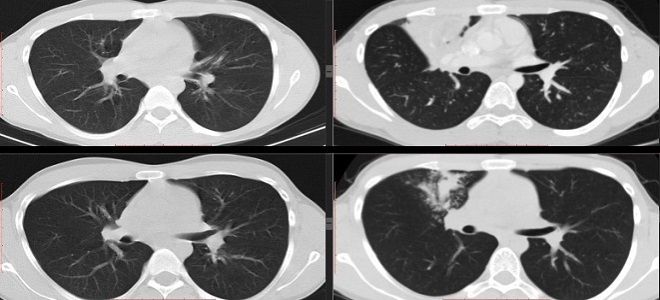

Процедура КТ при подозрении на коронавирус довольно проста для пациента. Во время обследования он должен оставаться неподвижным, в то время как рентгеновский аппарат вращается под определенным углом и с заданной скоростью. В результате врачи получают послойные изображения легких с шагом в 1 мм. Эта методика позволяет выявить даже самые незначительные поражения легких, связанные с коронавирусом.

Обычная рентгенография предоставляет лишь плоское изображение, не позволяя увидеть послойное состояние исследуемых тканей. Это создает трудности на ранних этапах, когда легкие поражены коронавирусом незначительно, и изменения могут быть незаметны. Для подтверждения диагноза при наличии типичных симптомов COVID-19 врачи часто назначают компьютерную томографию (КТ). Однако пациенты иногда выражают сомнения относительно необходимости этого исследования, задаваясь вопросом, действительно ли КТ может выявить коронавирус.

Важно понимать, что само по себе исследование не позволяет обнаружить вирус. Тем не менее, с его помощью можно выявить изменения в легочной ткани, характерные для коронавирусной инфекции. Эти изменения могут проявляться уже на 4-5-й день после попадания вируса в легкие. Врачи подчеркивают несколько ключевых причин для проведения КТ при COVID-19:

- Выявление признаков очагово-инфильтративных изменений легочной ткани, таких как «матовое стекло».

- Оценка состояния бронхиального дерева и наличие деформаций бронхов.

- Определение диаметра легочных артерий и лимфатических узлов.

- Обнаружение возможных новообразований в легких, а также их количество и размеры.

Первоначальные данные КТ при COVID-19 включают двустороннее многодолевое затемнение по типу «матового стекла» (GGO) с периферическим или задним распределением, главным образом в нижних долях и реже в средней доле.